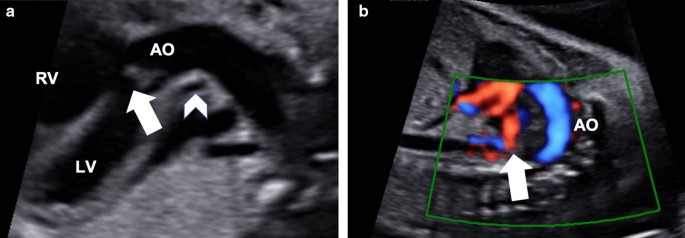

A 33-year-old pregnant Asian woman (gravida 1, para 0) was referred to our hospital at 24 weeks of gestation because of a suspected fetal heart anomaly on routine obstetric ultrasonography. The results of her prenatal laboratory tests were normal. Fetal echocardiography revealed a large ventricular septal defect (VSD) measuring 5 mm with a large overriding aorta (Fig. 1a). We also observed multiple major aortopulmonary collateral arteries (Fig. 1b). Therefore, the initial prenatal diagnosis was pulmonary atresia with VSD (PAVSD). A very atretic main pulmonary artery (MPA) can be seen in Fig. 1a retrospectively; however, we were not able to detect this artery at that time. The subsequent fetal echocardiography, which we performed at 26 weeks of gestation, revealed a highly atretic MPA from the right ventricle (RV) giving rise to the right pulmonary artery (RPA), without bifurcation (Fig. 2a). Instead of the bifurcation of the MPA, the left pulmonary artery (LPA) originated from the left subclavian artery (LSA; Fig. 2b, c). The echogenicity of the thymus was not definitive on prenatal echocardiography. On the basis of these findings, the fetus was diagnosed as having PAVSD with left PAD and 22q11.2 deletion syndrome. Considering the gestational age at diagnosis, we decided to postpone the genetic study to after birth. A female neonate was delivered by elective cesarean section at 376/7 weeks of gestation for the timed delivery, with a body weight of 2740 g, Apgar score of 8/9 points, heartbeat of 155 beats per minute, respiratory rate of 44 breaths per minute, blood pressure of 71/38 mmHg, and SpO2 of 88%. Multidetector computed tomography (MDCT) revealed a right-sided aortic arch, with the left-sided ductus arteriosus (DA) originating from the LSA and MAPCA. It also revealed a narrow RPA (2.7 mm) connecting with the MPA (2.7 mm), without connection with the LPA (2.7 mm size). The LPA originated from the left-sided DA originating from the LSA. Three-dimensional MDCT images showed the posterior aspect of the heart of the affected neonate (Fig. 3a–c).